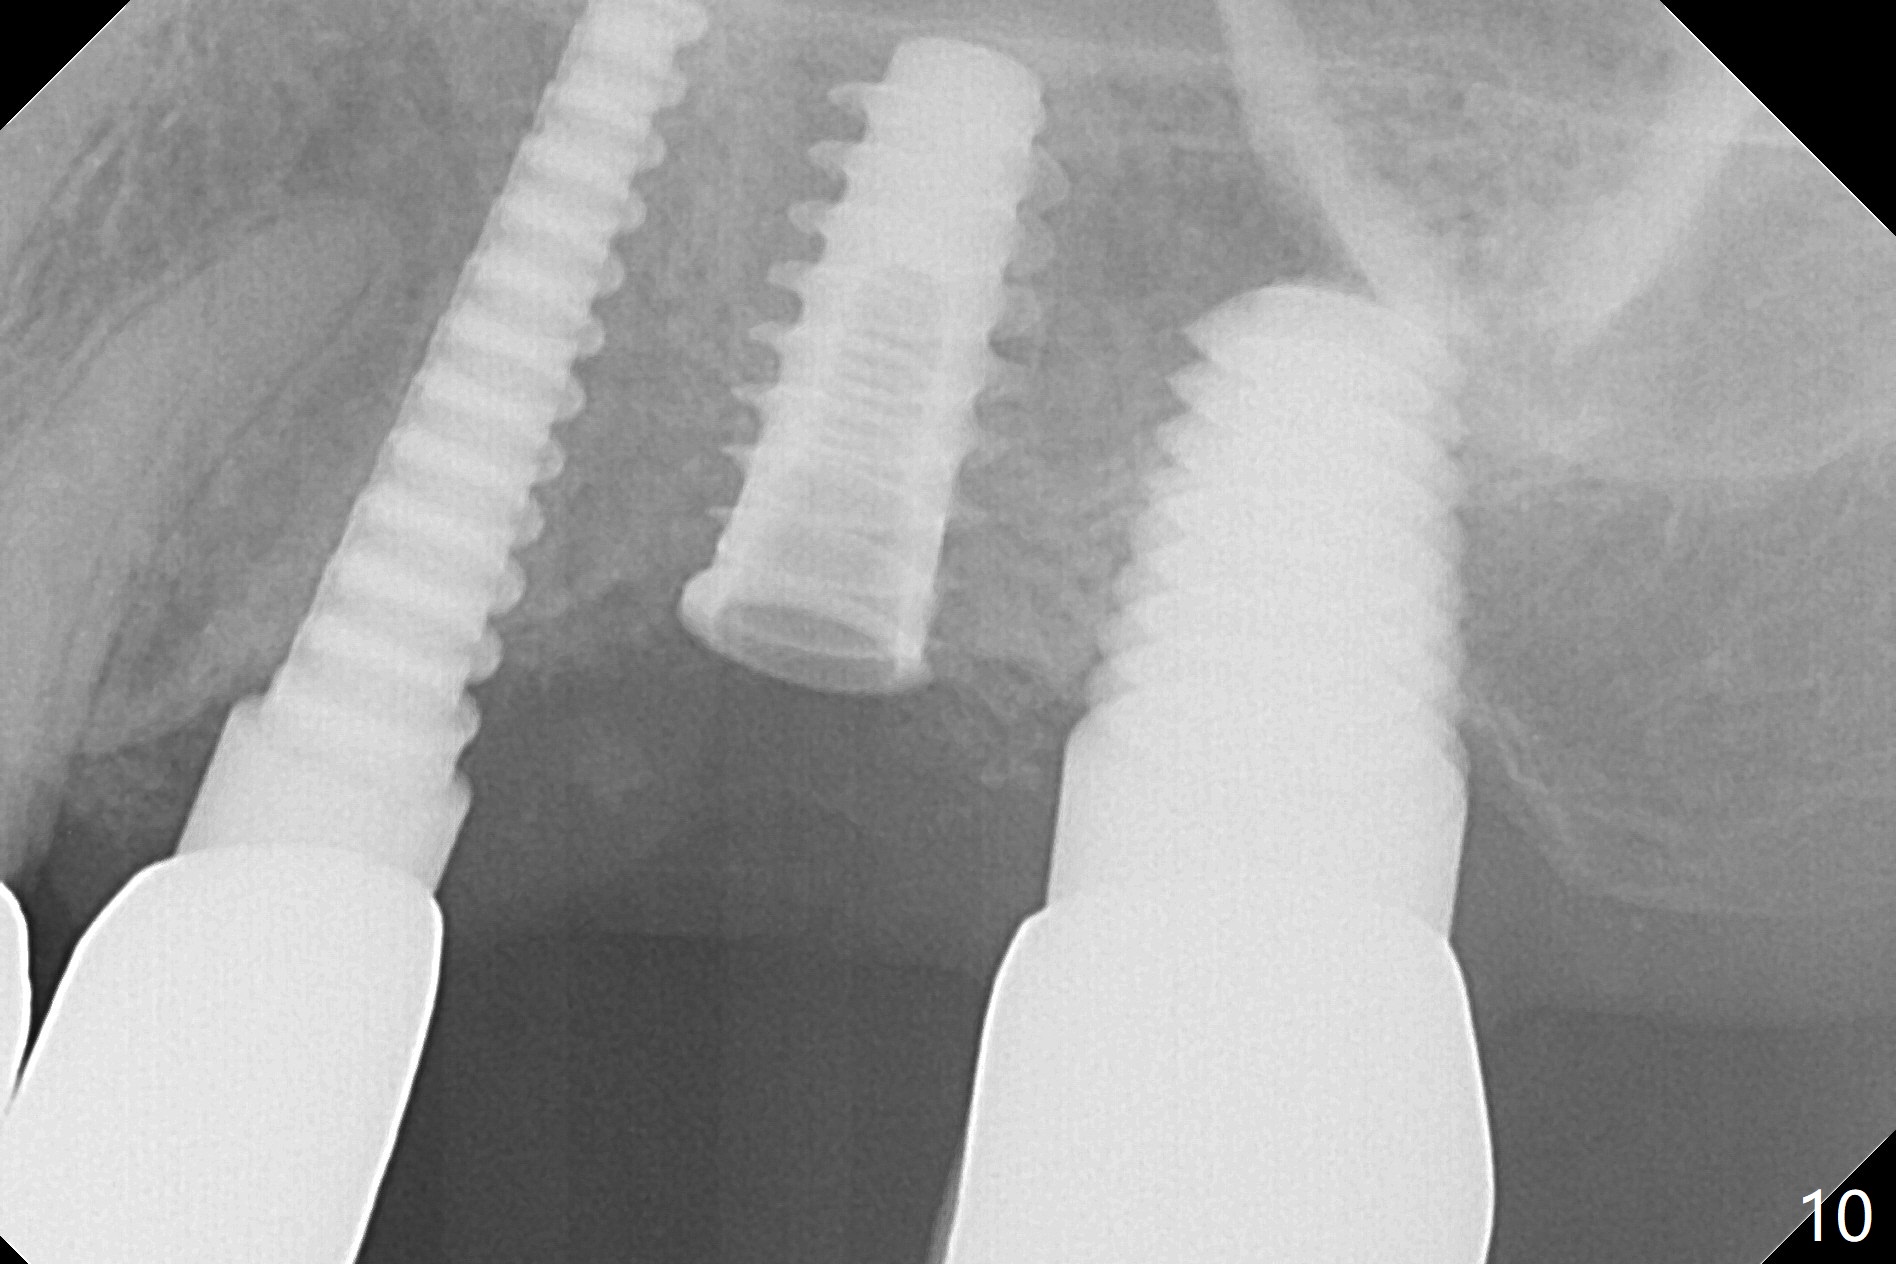

Initial osteotomy in the septum of the tooth #14 is 9 mm, approximately 2 mm from the sinus floor (Fig.1). Subsequent osteotomy depth is 11 mm, followed by insertion of a 4.5x11 mm dummy implant (Fig.2). After use of Magic Drill (MD) 4.8 mm for 9 mm, a 5x11 mm IBS implant is placed with sinus lift without additional bone graft (Fig.3 *). In contrast, autogenous bone (from MD) and Vanilla Graft are meticulously placed in the remaining socket (+) before and after placement of a 6.5x5.7(2) mm abutment. An immediate provisional is fabricated to close the sockets. There is buccal tenderness 1-3 months postop. There is distopalatal implant thread exposure. A healing abutment (5.5x2 mm) is placed. CT confirms thin buccal plate (Fig.4,5). It appears that the implant should have been as palatal as possible. The tenderness remains for the next 2 weeks. When the healing abutment is removed, the implant seems to have been placed shallow, ~ 1 mm subgingival (Fig.6). With local anesthesia, the implant is reversed to clean the coronal threads with Titanium brush and copious irrigation (Fig.7). The implant is then placed ~4 mm subgingival (Fig.8) and slightly subcrestal (Fig.9,10). It appears that the postop bone loss (Fig.9 *, as compared Fig.1,2) makes the implant look to be placed too shallow. When the implant is being placed deeper, the buccal plate feels intact. The early periimplantitis is apparently due to postop bone loss more than buccal placement, although certain degree of buccal bone resorption must occur. A 6x4 mm healing abutment is placed. Left facial swelling develops 2 days post implant elevation (Fig.11,12, as compared to preop (Fig.13)). The left maxillary sinus cloud (Fig.12) appears to be a false positive finding, since the same feature exists prior to implant elevation (Fig.13). Both sinuses look clear prior to implant elevation (Fig.14). Amoxicillin switches to Augmentin and Flagyl, since the patient is reluctant to have the implant removed. Finally the sinus infection is under control. The patient feels left facial swelling 9 months postop (5 months post elevation) and reports left nasal discharge ~ 1 month earlier. There is mild buccal plate tenderness. The implant seems to be buccally placed (Fig.15,16), although there is no significant change radiographically (Fig.17). The implant is removed with bone graft (Fig.18 *). To avoid complication and failure, an immediate implant at the upper 1st molar should be short and placed deep.